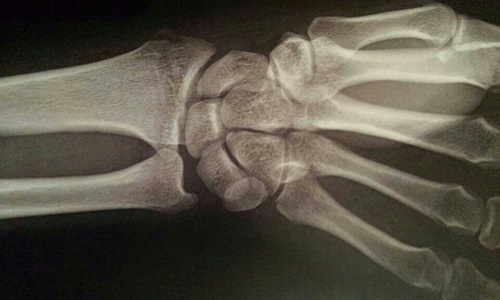

在全身各种关节脱位中,以肘关节脱位最多见,肩关节排在第二位,然后是髋关节。关节脱位的诊断比较容易,运动损伤性脱位的共同特征为有外伤史,患处关节疼痛,肿胀,关节功能丧失,有时可合并血管和神经损伤。关节脱位的体征也非常明显,一有明显的畸形,如肘关节脱位表现为肘关节向后明显凸出,肩关节脱位表现出肩部的曲线消失,形成方肩畸形等。二是发生弹性固定,即脱位后因骨头被关节囊、韧带卡住并伴随肌肉痉孪,患肢被保持在异常位置,如肘关节脱位被固定于半伸位,肩关节脱位会被固定在半外展位,患者以健侧手托着患侧前臂,头和上身都向患侧倾斜,喜欢坐位。三是关节盂所在部位空虚,即脱位后关节囊内摸不到原有的骨头,而在不该出现的地方可摸到脱位的骨头,如肘关节脱位可于肘前方摸到肱骨(上臂骨)远端,肘后部可摸到尺骨鹰咀(前臂骨)近端,肩关节脱位可在锁骨下(胸前上方)或腋窝处摸到肱骨头。当然,拍摄X光片可以明确诊断。

典型的关节脱位症状体征明显,患者都会及时赴医院摄X光片检查,诊断不难,并能得到恰当处理。但是在临床上也时有一些患者因损伤较轻,仅发生关节不完全脱位或者半脱位而被忽视,导致治疗延误。因此,对待关节处发生的损伤一定要格外当心,尤其是伤后关节疼痛,活动受限,或者出现畸形,那怕是轻微畸形均不可掉以轻心,而应及时到医院检查。需要强调指出的是,有些发生不完全脱位或者半脱位的患者有可能在受伤时或者发生后于不经意中活动关节获得复位,常听到“啪”的一声,关节活动得到恢复而以为“没事了”。这很可能导致不良后果。因关节中骨头虽然已经复位,但不完全脱位和半脱位导致的关节囊和韧带的损伤并不会立刻恢复,该关节还应固定休息2~3周才能康复。而不恰当的过早过频的关节活动可导致关节囊和韧带修复障碍,造成关节囊松弛,衍变成该关节习惯性脱位,那就更麻烦了。这种脱位多因第一次脱位治疗不当,导致关节囊松弛后发生,以后只要受到轻微损伤,甚至正常活动关节时范围稍过大即反复发作,故值得警惕。